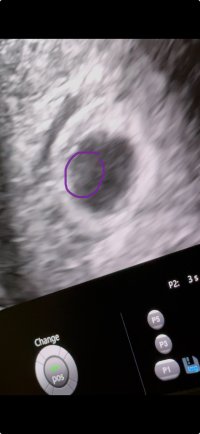

Ble dessverre satt tilbake fra 6+5 til 6+0, noe som er litt rart med tanke på stabil syklus, men da tok det vel litt tid fra EL til befruktning.